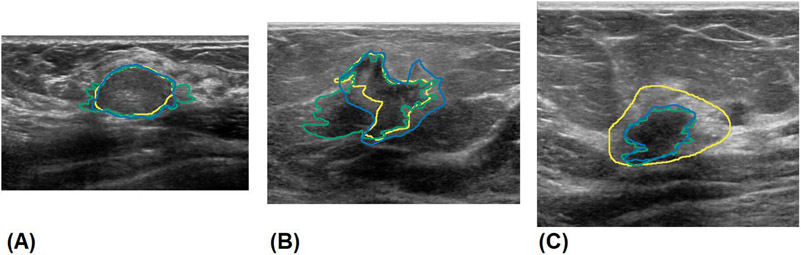

Fig. 1.

Manual segmentation of benign and malignant breast masses by experts. A) segmentations of a benign fibroadenoma, B) segmentations of a malignant invasive ductal carcinoma with indistinct margins, C) segmentations showing stylistic choice in segmenting hyperechoic rim. The results of experts 1, 2, and 3 are shown in green, blue and yellow, respectively.

Clinical US images were obtained from patients with suspicious breast masses from different institutions using different equipment and settings. Written consent was obtained from all patients, along with proper institutional review board approval from the Mayo Clinic, while being Health Insurance Portability and Accountability Act compliant. Patients older than 19 years who underwent biopsy after US imaging for breast cancer were included in this prospective study. Patients who had breast implants or abnormalities or who had previously undergone any breast surgical procedures were excluded from the study. A total of 733 patients participated, resulting in 2,312 US clinical images from multiple orientations, which were manually segmented to provide a label. Additionally, 295 cineclips from 118 patients undergoing breast ultrasound scans were used to augment training with 28,025 additional frames. Cineclips from a previous study on 455 thyroid nodules were obtained for pretraining [20]. A subset of 121 breast US images from 85 patients were distributed to three experts (two trained radiologists and one highly expert sonographer) for breast mass segmentation. Of the total, 40 patients had malignant masses, 44 patients had benign lesions, and 1 patient was categorized as atypical and high risk, as confirmed by biopsy. The mean patient age was 57±15.0 years. There were 65 patients classified as BI-RADS 4, 18 patients classified as BI-RADS 5, and 2 patients classified as BI-RADS 6. The training set comprised 1,305 images from 486 patients, the validation set consisted of 433 images from 162 patients, and the test set comprised 121 images from 85 patients. Images from patients in the test set that had not been segmented by the experts were excluded from the training or validation set to prevent cross-contamination. The sets were divided such that no patient appeared in more than one dataset to prevent cross-contamination of data that might artificially inflate performance. The test set was labeled by three experts, and the training and validation data were segmented by the research technologists experienced in breast US. Each expert was given every US image associated with the clinical exams, including shear wave images, Doppler images, and images marked with calipers. Segmentation was performed using the software at the discretion of the experts. Figure 1 depicts manual segmentation by experts for benign and malignant breast masses. Malignant nodules tend to be more diverse and challenging, with ambiguous boundaries and complex geometries, featuring projections, spiculations, and heterogeneous echogenicity [5, 22]. An additional source of interobserver variance is disagreement over the inclusion of hyperechoic rims, a band of hyperechoic tissue surrounding some hypoechoic lesions. An example of a manual segmentation variance in a lesion with a hyperechoic band is shown in Figure 1C.